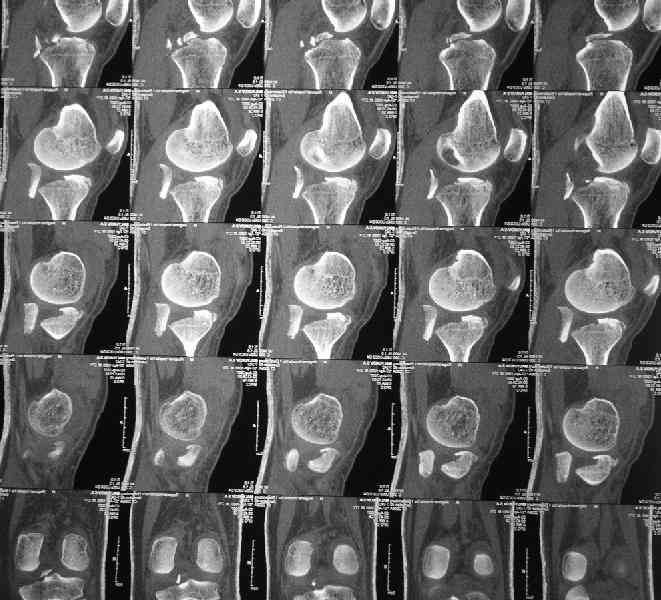

Молодой человек(27 лет) получил травму в ДТП 2 недели назад(23.07).Хотелось бы получить ответы на следующие вопросы:1.Какой доступ предпочесть?

2.Чем фиксировать? Заранее спасибо за конструктивные ответы.